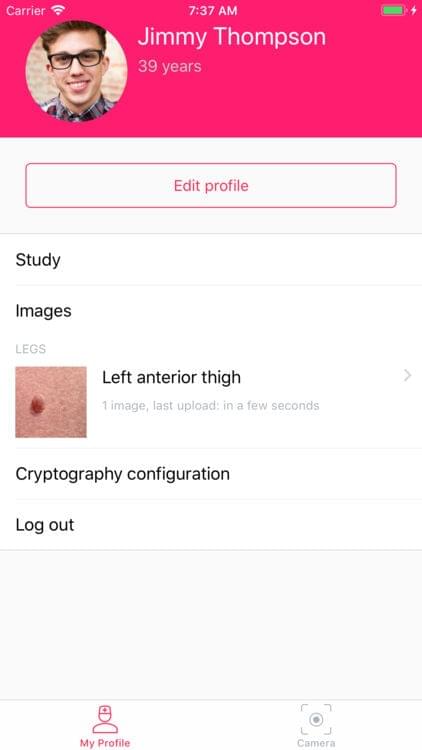

Skin — Patient Profiles

Skin is a digital health imaging app for tracking of moles and skin lesions. The platform is targeted towards academic researchers, physicians and patients looking to integrate a robust sharing platform for the management and surveillance of dermatological conditions. This app gives medical institutions and physicians a secure option to create scalable studies with hundreds of patient participants. The tool is intended to help support the creation of an intelligent model for the accurate diagnosis of skin diseases.